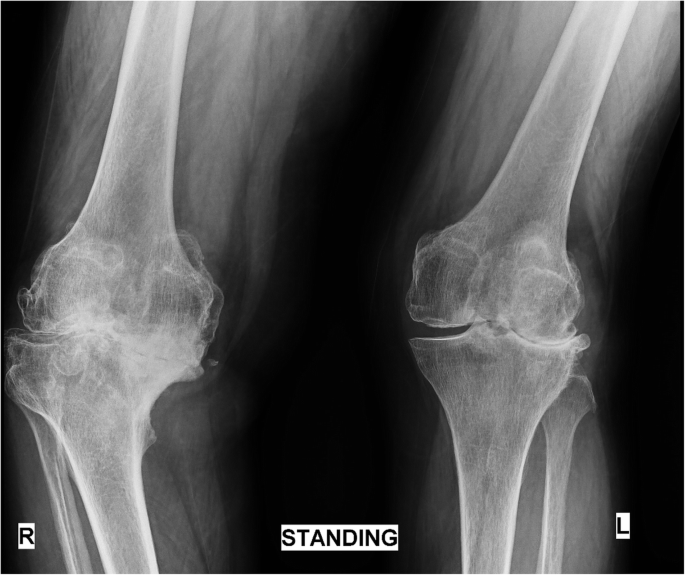

Windswept Deformity Diagnosis

To diagnose windswept deformity, various radiological tests including X-rays and MRI are recommended. Osteochondritis is the general feature of this deformity. It depends on the severity of the case. In few cases, the distal part of the femur is involved, while in some cases tibia is involved. There is a possibility that both can be affected as well.

The portion of epiphysis becomes wedge-shaped. Along with the radiological tests, a complete blood count test is also recommended to check the minerals and blood cell count. The imbalance in potassium, magnesium, and sodium can worsen the condition. It is advised to seek immediate help whenever there is a hint of deformity.